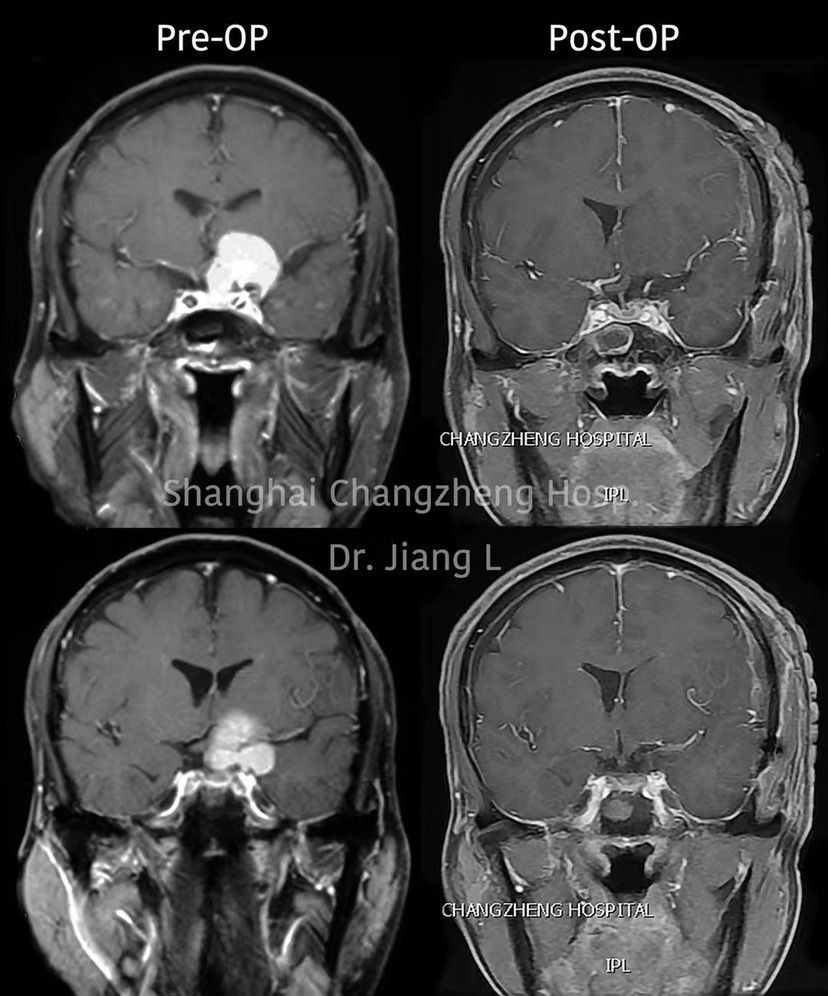

MRI检查:

术后MRI复查: